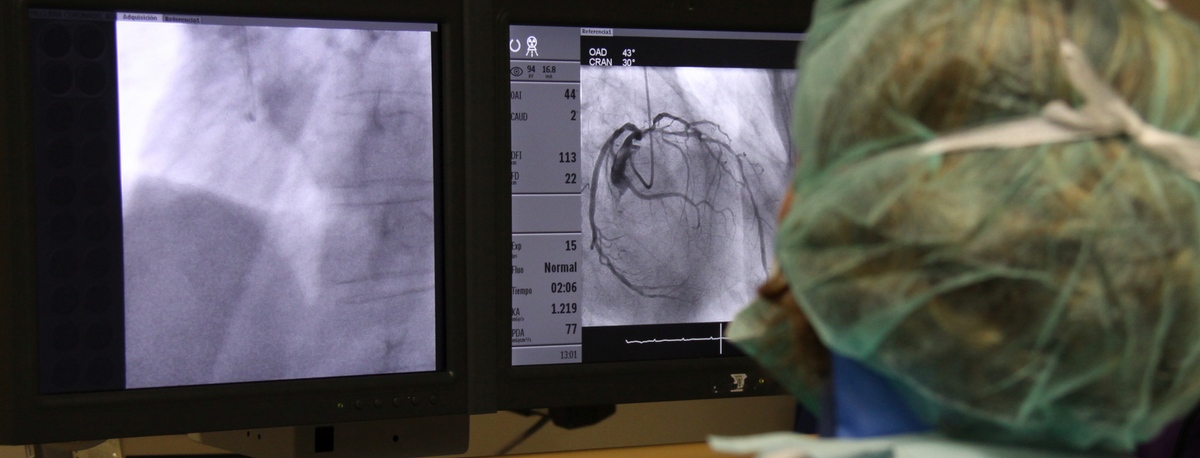

Teknon Cardiology Institute

Treatments and Specialities

The institute is staffed with specialists in angiology, vascular surgery, and endovascular surgery, who handle everything from diagnosing to monitoring circulatory system illnesses.Cerebral embolism and pulmonary thromboembolism are some of the leading causes of death due to vascular problems.

Our team specialises in minimally invasive techniques, using endovascular techniques without surgery, which allow vascular prostheses to be implanted to resolve dilations or aneurysms of the arteries. We also offer all treatments for venous and peripheral arterial disease, including carotid artery disease.